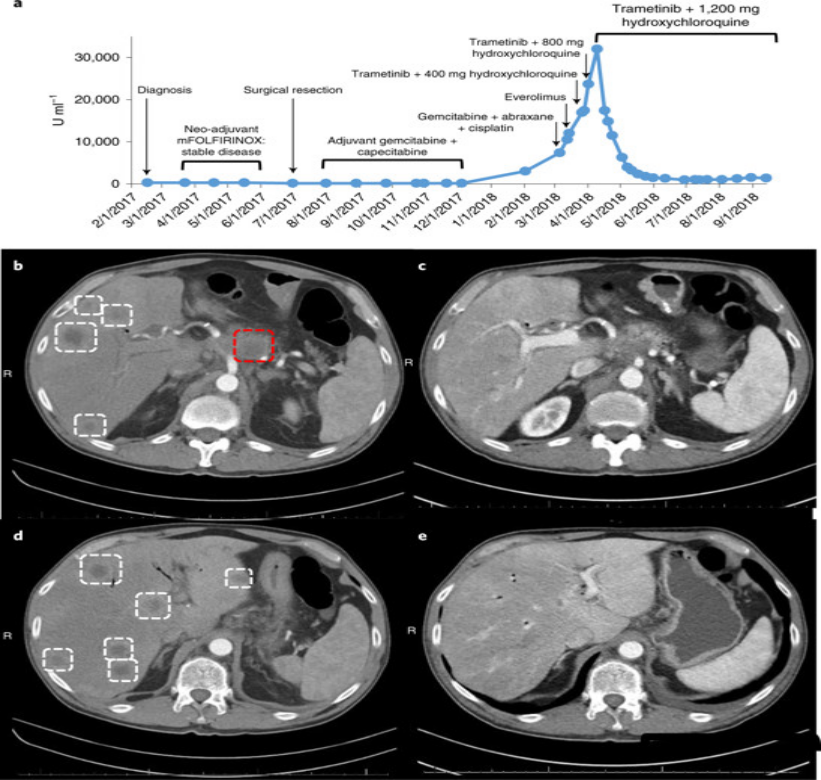

这种联合疗法的效果在一位晚期胰腺癌患者身上同样到了证实,这位患者在手术后,接受了几次化疗,但不幸的是癌症复发并转移了,目前已经没有很好的治疗方案。

这名患者接受了 trametinib和hydroxychloroquine治疗,令患者和医生震惊的是,奇迹出现了,2个月内,患者的胰腺癌标志物CA 19-9的血液水平下降了95%。4个月后,他体内的癌症数量减少了50%。对于胰腺癌来说,这是一个非常了不起的反应!